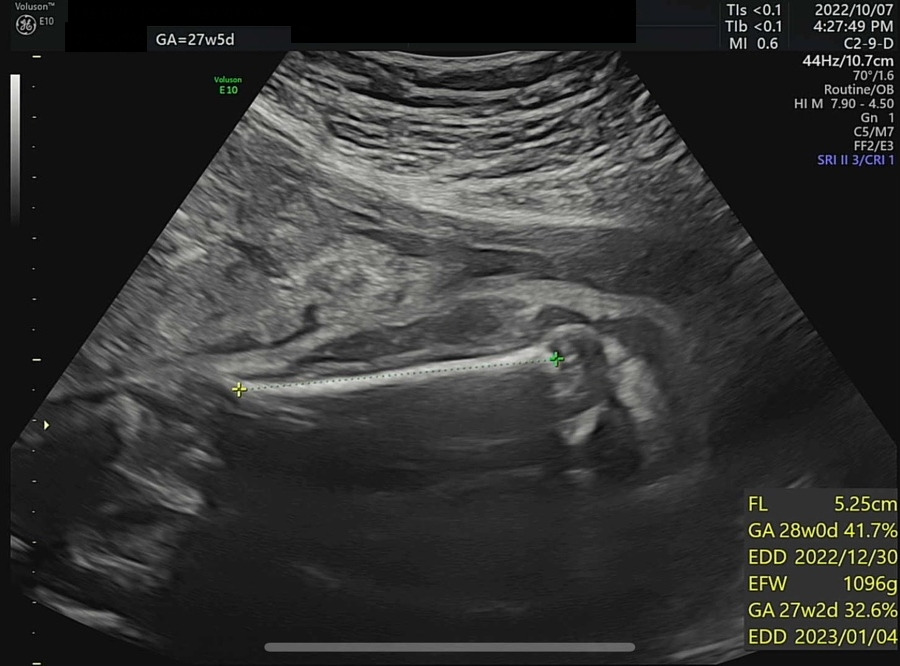

오늘은 병원에서 4D 입체 초음파를 찍기로 예약한 날이다. 입체 초음파는 아기의 모습을 입체적으로 사진 찍듯이 볼 수 있는데, 27주쯤에 찍어야 아기도 통통하게 살이 올라 예쁘게 찍힌다고 하여 이때 예약했다. 초음파실에 들어가서 아기가 주수에 맞게 잘 컸는지부터 확인했다. 2주 전 860g 정도였던 써니는 벌써 1kg를 돌파하여 1096g이 되었다. 임신 28주 이후에 체중이 1000g을 넘은 아기는 조산하여도 NICU(Neonatal Intensive Care Unit, 신생아 집중치료실)에서 치료를 받을 경우 생존 가능성이 95% 이상이다. 가장 친한 친구 중 한 명이 NICU 간호사인데, 매번 써니의 체중을 물어보았었다(직업병..?). 이제 1kg를 넘었으니 혹시나 세상에 일찍 나와도 이모한테 가면 살 수 있다. 그래도 이모 일터에는 가지 말자 써니야...

왼쪽부터 복부 둘레, 허벅지뼈 길이와 예상 체중(머리 좌우직경과 복부 둘레로 예측), 팔뚝뼈 길이

KakaoTalk_20221010_121559048_06.jpg 기계는 서양 데이터 기반이라 한국 아기는 이에 비해 머리가 조금 크고 몸통은 좀 작고 다리도 좀 짧다고... (다리는 기니까 다행...)